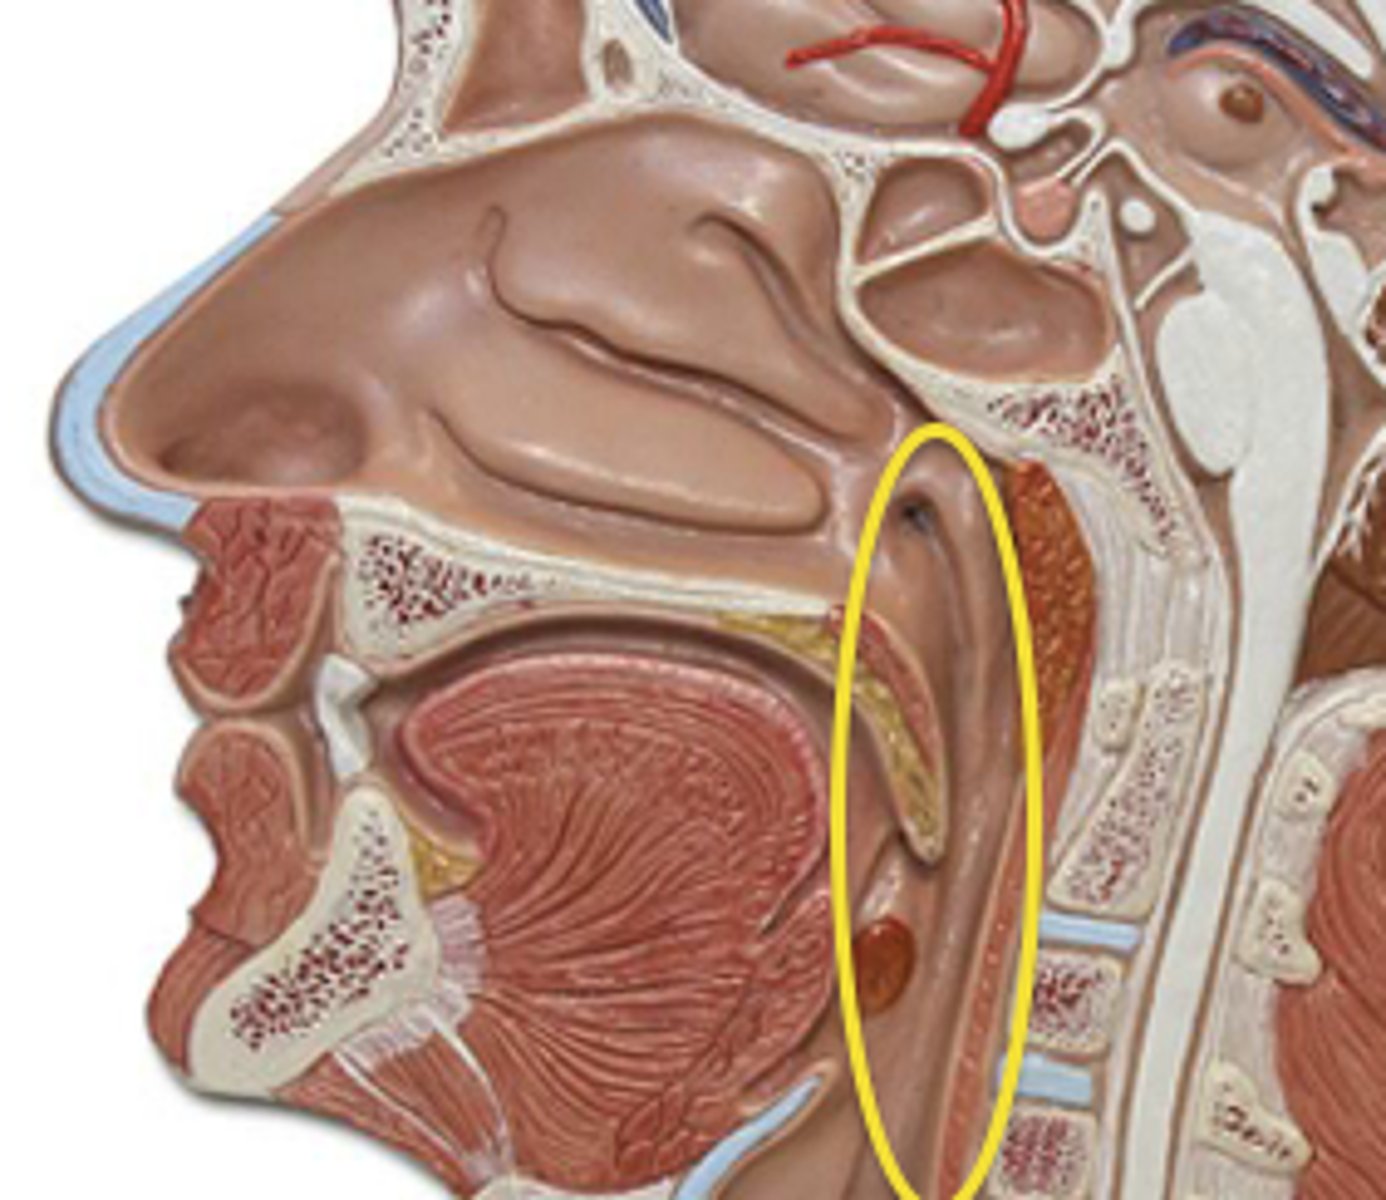

Pharynx

The membrane-lined cavity behind the nose and mouth, connecting them to the esophagus.

Nasopharynx

Region of the pharynx at the back of the nose and above the soft palate

Pharyngeal Orifice of Pharyngotympanic Tube

The base of the cartilaginous portion of the auditory tube

Oropharynx

Central portion of the pharynx between the roof of the mouth and the upper edge of the epiglottis

Laryngopharynx

Lower part of the pharynx, just below the oropharyngeal opening into the larynx and esophagus

Larynx

Voice box; passageway for air moving from pharynx to trachea; contains vocal cords

Epiglottis

A flap of cartilage at the root of the tongue, which is depressed during swallowing to cover the opening of the windpipe